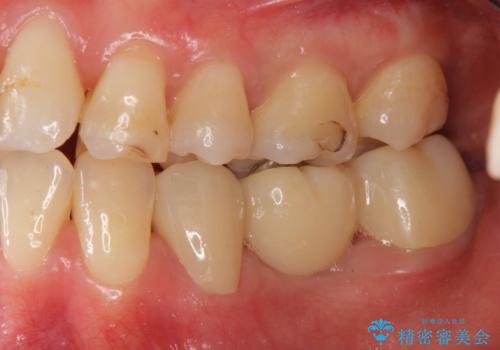

途中全体矯正をはさみ、根の向きが並行になった状態でブリッジを入れることができました。

- 36.3万円 (ジルコニアクラウン 10万円×3、仮歯1万円×3)費用は治療当時の料金となります